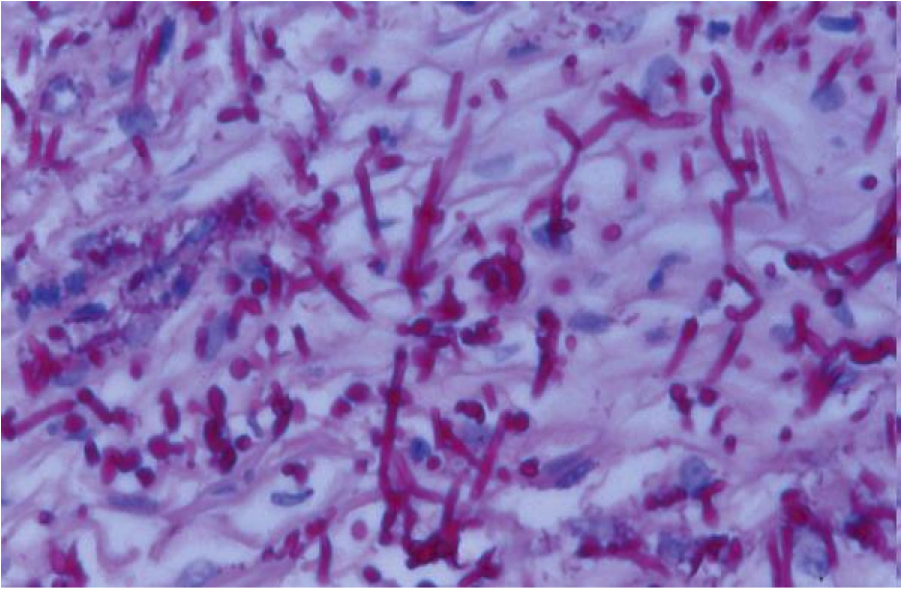

Candida esophagitis

- Immunosuppressed, Diabetics, recent Abx

- Pseudohyphae